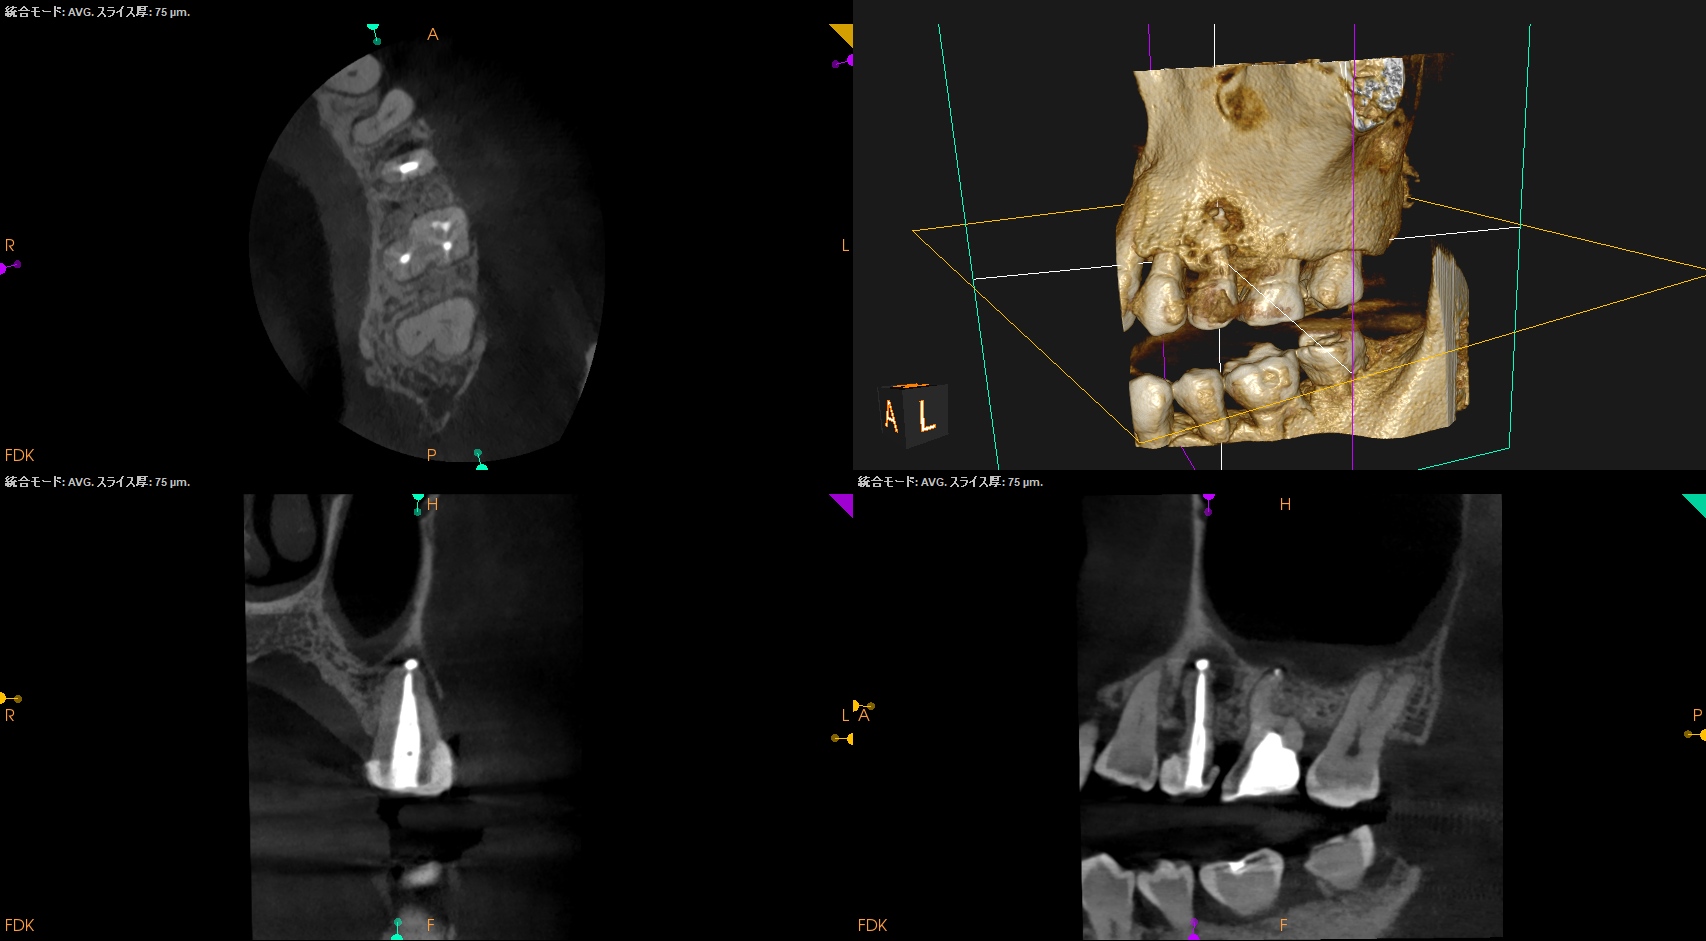

作業長が術前に予測したCBCTでの作業長に近似していること

を。

これが、

CBCTの威力

である。

ということで、術後にPA, CBCTを撮影した。

#14

MB1

MB2

DB

P

#14 Pは外部へBC sealerが溢出したが、

文献的には押し出されたそれは、

で、問題はないと考える。

当歯科医院のケースでもそれが最終的には臨床上は消失しているように見えて症状も消失していることが確認されているので問題視してない。

#13